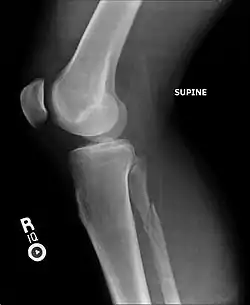

![]() | |

| Radiograph showing a Maisonneuve fracture of the proximal fibula | |